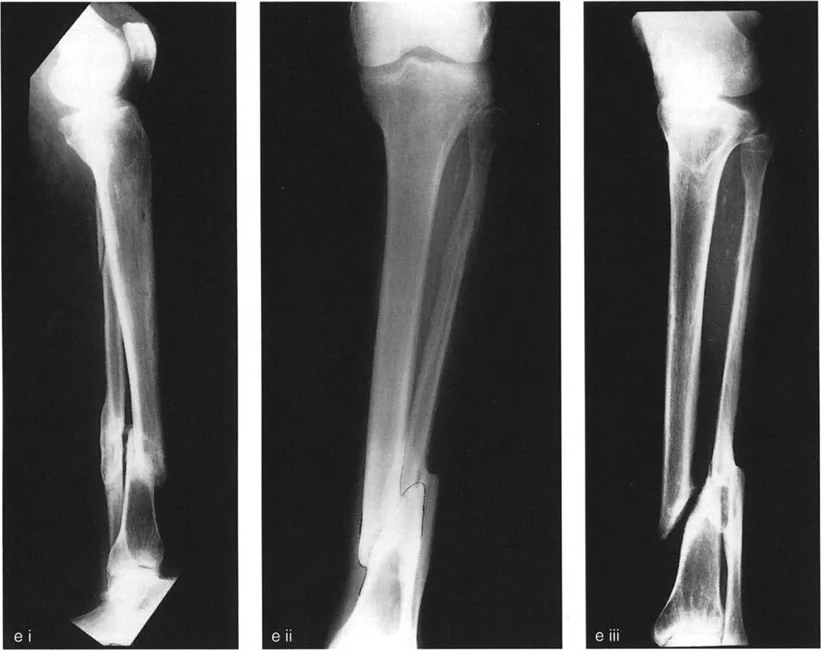

2. التصوير بالأشعة السينية (X-rays)

تعتبر الأشعة السينية هي الأداة التشخيصية الأساسية لتشوه الانزياح. يتم التقاط صور متعددة من زوايا مختلفة (عادةً الأمامية-الخلفية AP والجانبية LAT، وقد تشمل صوراً مائلة Oblique) للحصول على رؤية شاملة للتشوه.

- تحديد مستوى الانزياح: تظهر الأشعة السينية بوضوح المنطقة التي حدث فيها الانزياح.

- قياس حجم الانزياح (Magnitude): يتم قياس المسافة التي تحركها أطراف العظم بالمليمترات.

- تحديد اتجاه الانزياح (Direction): يتم وصف اتجاه الجزء البعيد من العظم بالنسبة للجزء القريب (مثلاً: أمامي، خلفي، إنسي، وحشي، أو مزيج منها).

- تحديد مستوى الانزياح (Level): يتم تحديد المنطقة التي تتداخل فيها أطراف العظم، والتي غالباً ما تكون مرتبطة بالتقصير.

- تقييم التلامس العظمي: تساعد الأشعة السينية في تحديد مدى فقدان التلامس بين أطراف العظم، وهو مؤشر مهم لعدم التئام الكسور.

- الأشعة المائلة (Oblique Radiographs): في بعض الحالات، قد لا يظهر الانزياح بوضوح في الصور الأمامية-الخلفية أو الجانبية، مما يستدعي صوراً مائلة للكشف عن التشوه الحقيقي، خاصة في حالات الانزياح في المستويات المائلة.